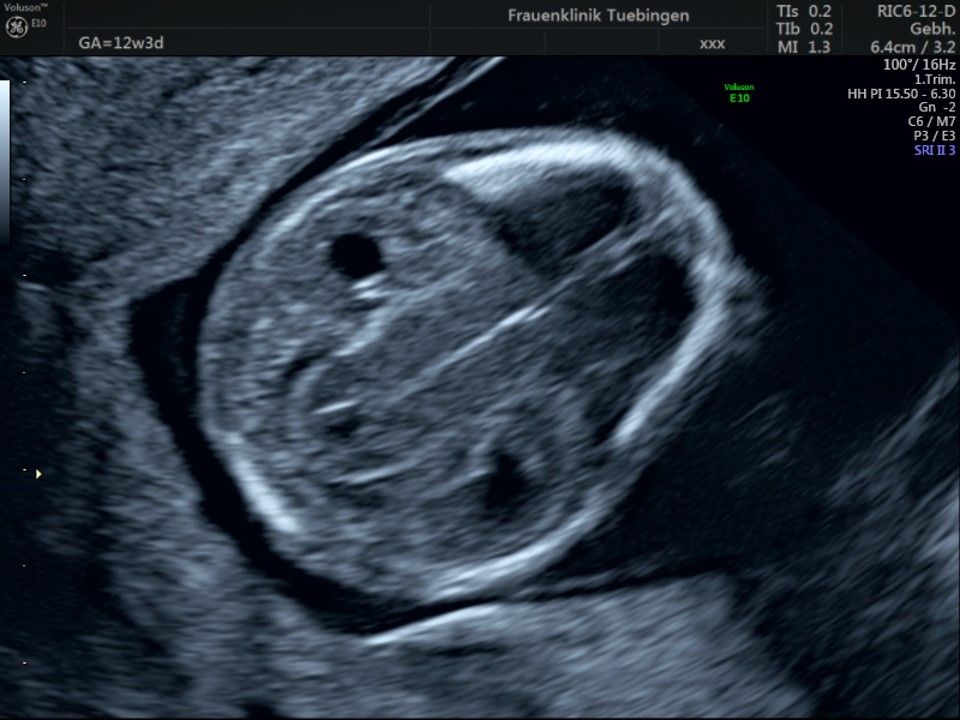

Im Rahmen des Ersttrimester-Screenings untersuchen wir die Organe des Feten mittels Ultraschall. Dabei machen wir auch gerne ein Bild für Sie.

Obwohl der Fet zu diesem Zeitpunkt erst zwischen 5 und 8cm groß ist, lassen sich bereits etwa die Hälfte aller schwerwiegenden Fehlbildungen erkennen bzw. ausschließen. Sollten wir eine Auffälligkeit sehen, werden wir mit Ihnen den Befund und das weitere Vorgehen ausführlich besprechen.

Fetale Anatomie

Das Ergebnis der Ultraschalluntersuchung ist wegweisend. Dabei wird der Fet vermessen, die Organe werden untersucht und die sonographischen Marker zur Risikoberechnung für Chromosomenstörungen werden beurteilt. Das sind: die Nackentransparenzdicke, Nasenbein sowie der Blutfluss in der rechten Herzhälfte und im Ductus venosus, einem Gefäß in der Leber des Feten.